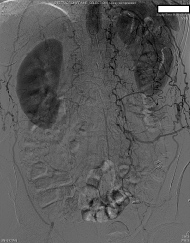

Preoperatively, the surgery service was queried by the anesthesiologist as to whether the routes of collateralization to the lower extremities were known. The response indicated that there had been intraabdominal collaterals demonstrated on angiography from the radial artery catheterization upon admission. The patient was then transported to the operating room, and a radial arterial line was placed during preoxygenation and prior to induction. After further consideration, the surgeon requested a delay of induction of anesthesia for further angiography review. Upon examination, a large right inferior epigastric artery was noted on the preoperative catheterization films, suggesting that collateral blood from the right internal mammary artery may supply the right lower extremity. The origin of collateral flow, however, could not be determined. Existing angiography was also unable to clearly demonstrate the collateral blood flow to the left lower extremity. At this point, the case was aborted before induction of anesthesia, and further angiography studies were ordered in consultation with a vascular surgeon. A subsequent aortogram and angiography of the internal mammary arteries demonstrated that collateral flow to the lower extremities was dependent on both the left and right internal mammary arteries (Figure 1, Figure 2 and Figure 3). Gastroepiploic artery was not considered as an alternative to the LIMA because of lack of institutional experience with the procedure.

Figure 3: Angiogram demonstrating collateral flow to the lower extremities due to aortic occlusion.